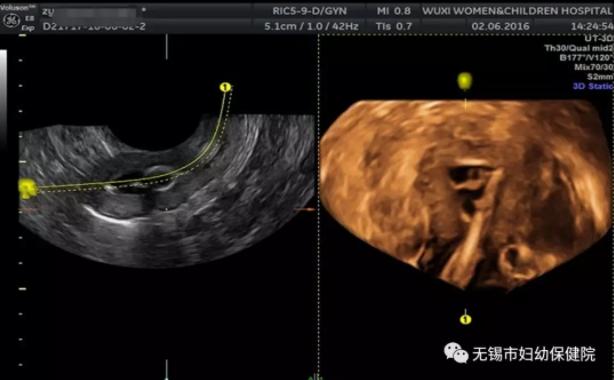

是经阴道置入一次性宫腔通水管,通过导管推注造影剂,在超声造影条件下观察造影剂在子宫腔、两侧宫角及两侧输卵管内的走行和分布情况,以及造影剂经伞端向盆腔溢出和弥散的情况。

四维超声输卵管造影技术具有安全、有效、经济、无辐射、无创伤、过敏机率低、患者痛苦小、重复性好、不影响受孕时间等优势。

此项检查项目可以将检查全程记录并存储,便于结果的观察分析及治疗前后疗效的对比分析。还可进行二次造影,比较两次造影的结果,增加诊断信心。

目前,四维子宫输卵管超声造影技术已成为输卵管通畅性检查的首选方法,同时也是诊断子宫畸形与宫腔疾病重要的辅助检查方法。通过增加输卵管内的流体静压力对输卵管产生挤压及分离作用,还能够克服由于输卵管括约肌痉挛所致的输卵管不通等情况。